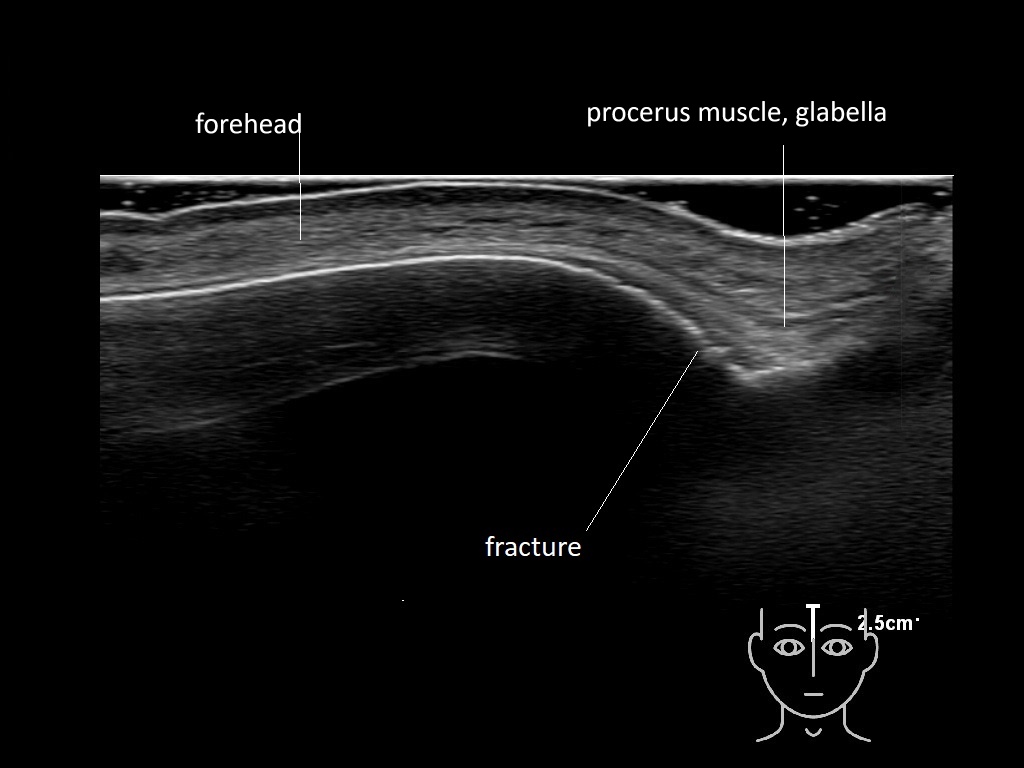

In this section you will learn more about the different layers of the face with the use of ultrasound. When you click on the secondary ultrasound image, you will see the different structures as an overlay. This will help to train yourself to recognize the different layers of the face.

Study the first image to recognize the different layers. If you are sure about the layers, swipe to the second image to view the answer (if applicable).